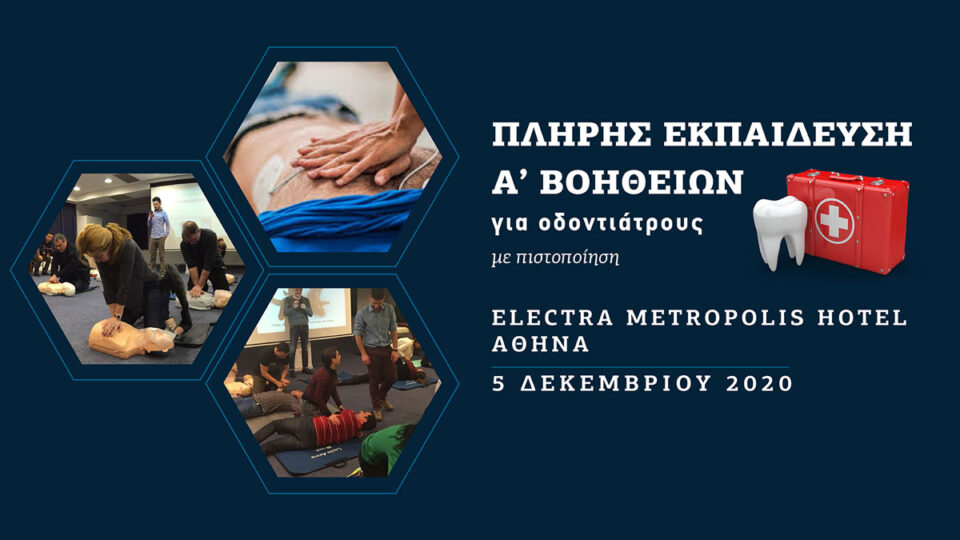

Πλήρης εκπαίδευση Α’ βοηθειών για οδοντιάτρους με πιστοποίηση (Αθήνα)

€166.00

Ημερομηνία διεξαγωγής: 5/12/2020 (Αθήνα)